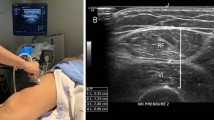

Three studies reported data on thigh muscle thickness through the average compression index measured by ultrasonography [30, 31, 35]. The combined findings of the meta-analysis revealed a statistically significant increase in average compression index (MD = 0.07, 95% CI 0.00 to 0.14, p = 0.04, I2 = 0%) (Fig. 5).

Observations revealed a noticeable increase in thigh circumference. While thigh circumference may not serve as a direct indicator of thigh muscle mass, Zenith et al. employed ultrasound as a method to evaluate thigh muscle thickness alongside thigh circumference in the studies under consideration [30]. The findings of their investigation suggest that the observed increase in thigh circumference can be attributed to the growth of muscular tissue. Likewise, in the study by Aamann et al., the experimental group showed an increase in both thigh circumference and fat-free mass. This indirectly confirms that the rise in thigh circumference is associated with muscle growth [36]. Furthermore, the pooled data on average compression index indicated a significant increase in thigh muscle thickness.